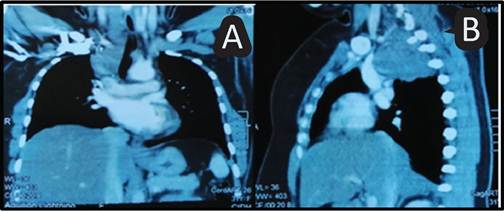

Paciente femenina 31 años de edad, con masa mediastinal posterior que desplaza estructuras adyacentes a la vía aérea (Ver Figura 1 A y B), sin antecedentes de mareo, síncope, palpitaciones; fue ingresada con plan de realizar exéresis de la masa, la que fue realizada por toracotomía posterolateral derecha, abordando la cavidad torácica y extrayendo masa pétrea y nodular adherida a pulmón, sin complicaciones transoperatorias inmediatas, con un electrocardiograma inicial sin alteración, se traslada a la Unidad Cuidados Intensivos (UCI), para soporte de ventilación mecánica invasiva durante 24 horas, se realiza extubación, presentando buena tolerancia y traslada a cuidados intermedios. Al día siguiente, la paciente presenta sincope, asociado a episodios de taquicardia alternando entre fibrilación auricular y taquicardia ventricular sin inestabilidad hemodinámica (Ver Figura 2-A), requiriendo oxigenación con sistema de alto flujo e infusión de amiodarona hasta lograr la reversibilidad de arritmias cardiacas; a nivel del electrocardiograma se observa la persistencia del ritmo de preexcitación (Onda Delta), que caracteriza al Síndrome de WPW (Ver Figura 2-B).